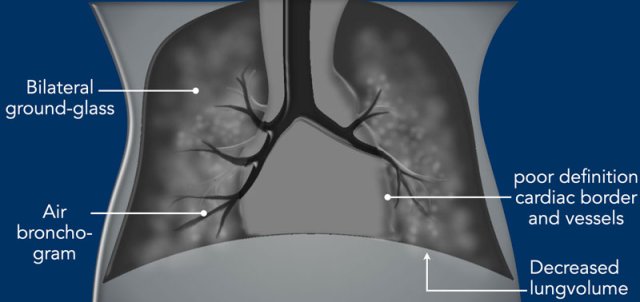

Imaging

• Decreased lung volume on chest radiograph unless the patient is on ventilator.

• Bilateral symmetric ground glass opacities.

• Air bronchograms can be visible into the periphery.

• Poor definition of the cardiac silhouette and pulmonary vessels, as a result of less aerated lung parenchyma.

• Usually no pleural effusion.Radiological appearance can be asymmetric immediately after minimally invasive surfactant therapy (MIST) and can mimic for example neonatal pneumonia.